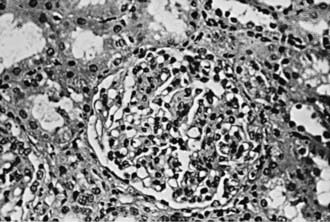

Focal and segmental mesangial proliferation and increased mesangial matrix are seen in the glomerulus (Fig. 504-1). Renal histology demonstrates mesangial proliferation that may be associated with epithelial cell crescent formation and sclerosis. IgA deposits in the mesangium are often accompanied by C3 complement (Fig. 504-2).

Figure 504-1 Light microscopy of immunoglobulin A nephropathy demonstrating segmental mesangial proliferation and increased matrix (×180).